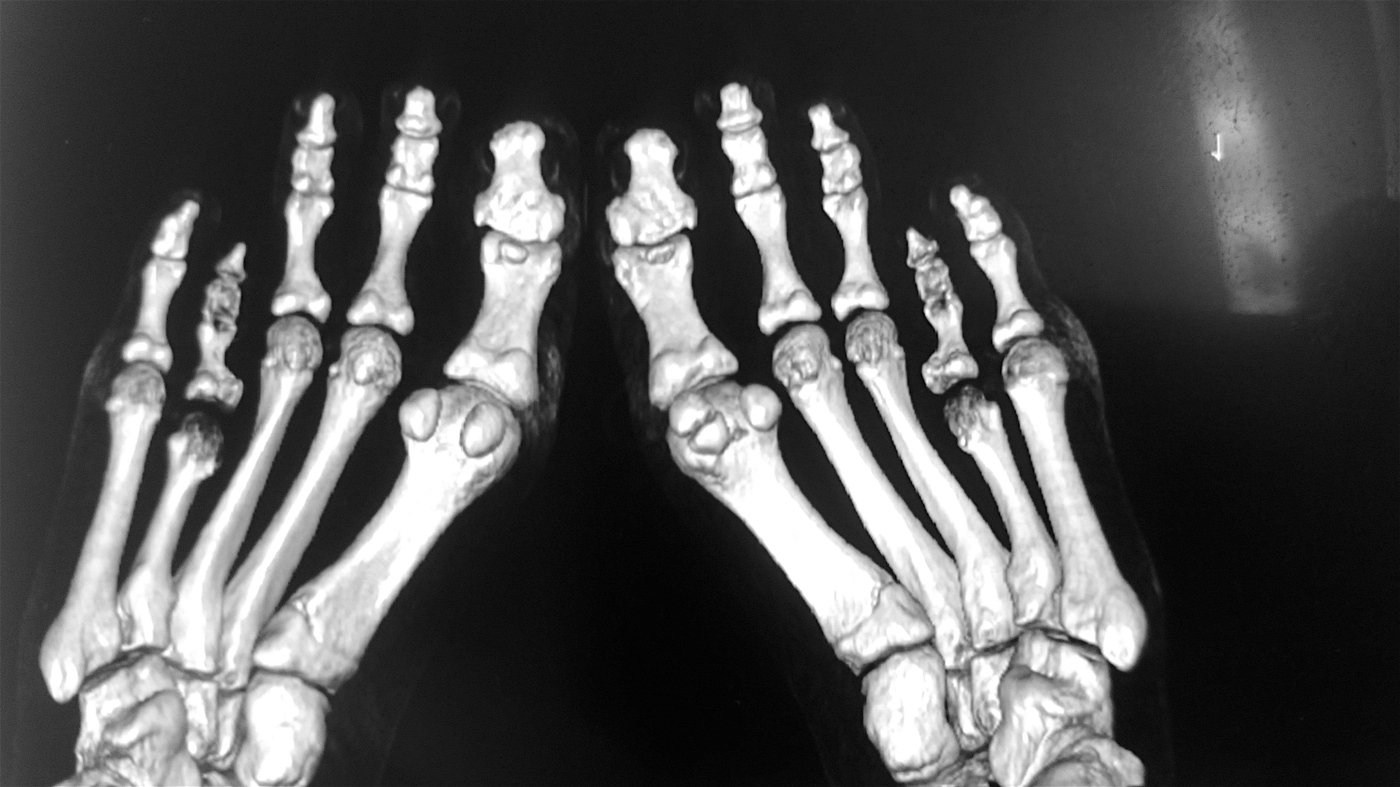

Случай брахиметатарзия, операция остеотомия с аллопластикой бикортикальным трансплантатом  "Лиопласт".